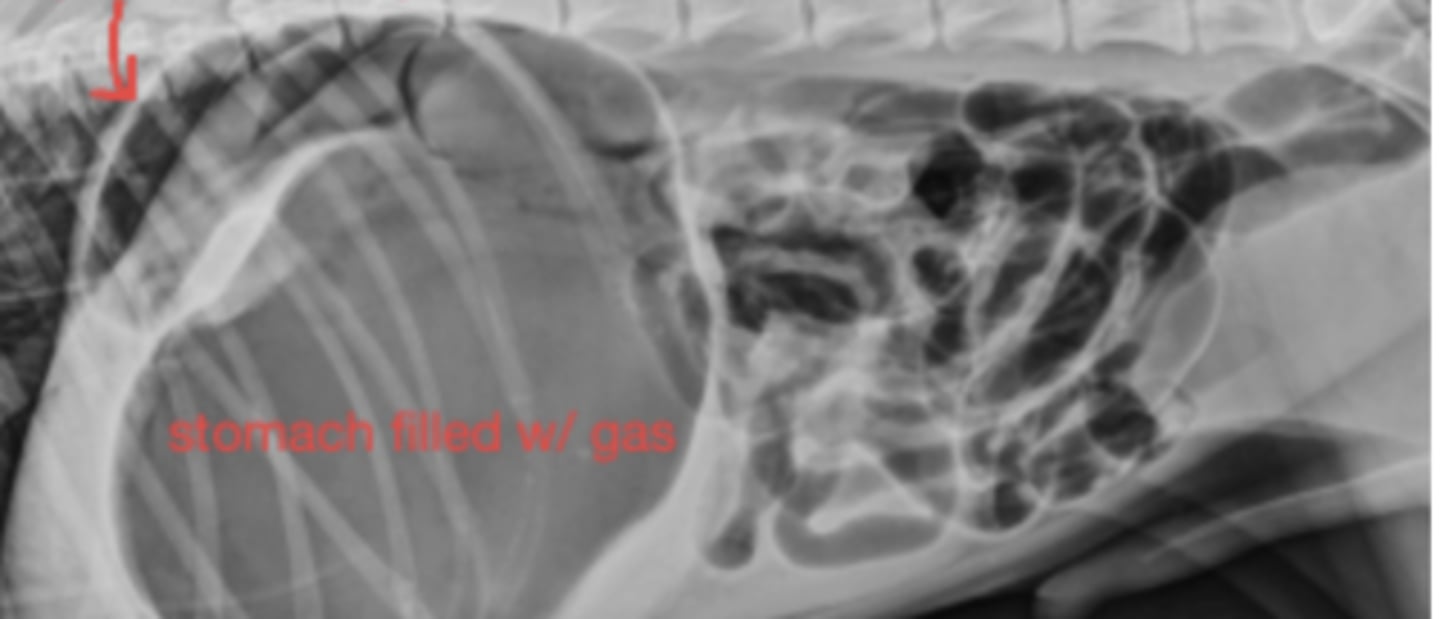

GDV

10 yo lab with abdominal distention, panting- what has caused this?